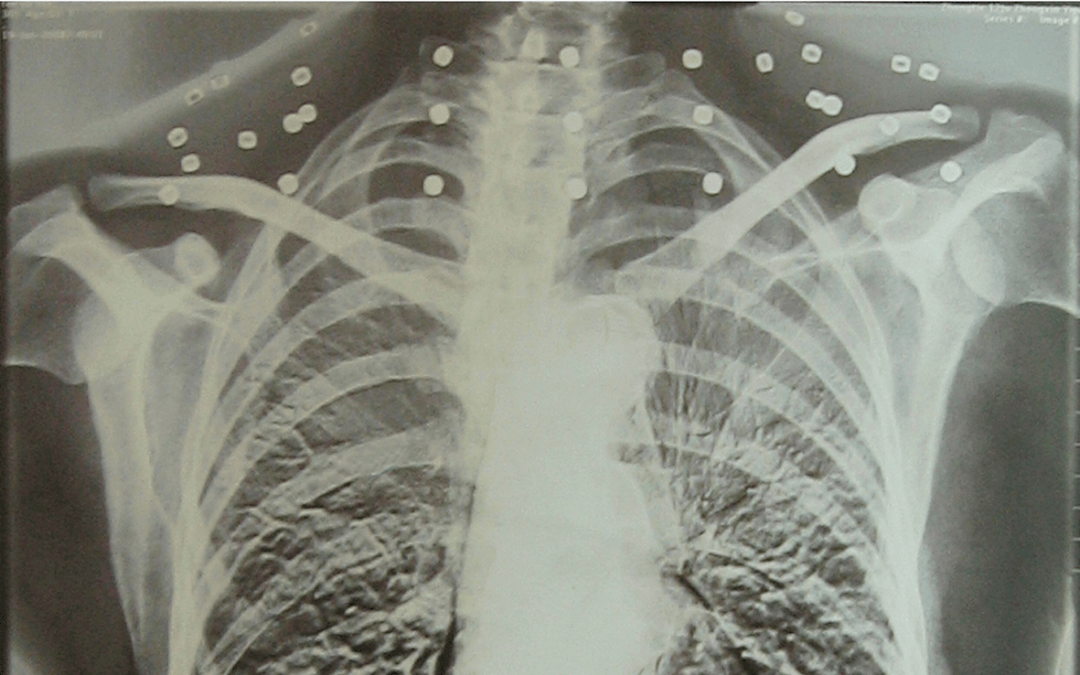

这张照片

是今年82岁的吴以先老人

拍摄的一张CT照

但实际上是

吴以先的颈部和腹部

共分布着33枚弹片

但是打进身体里的弹片

一直留在了体内

他体内的弹片都没有取出

这是他与战友并肩作战的见证

是他的勋章

与吴以先身上那33枚弹片

一起永远烙印在他心中

33枚“军功章”

是一名军人的光荣